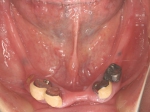

両側5歯症例

両側5歯症例両側5歯症例両側5歯症例 主訴-義歯のバネが壊れて手前の歯が痛んできた。 術前(旧義歯装着、鏡像) 術前(下顎粘膜面、鏡像)術前(下顎粘膜面、鏡像)術前(下顎粘膜面、鏡像) 術前レントゲン術前レントゲン術前レントゲン 術前口腔内(正面観)術前口腔内(正面観)術前口腔内(正面観)

術後(鏡像)術後(鏡像)術後(鏡像) 術後口腔内(正面観)術後口腔内(正面観)術後口腔内(正面観)もう入れ歯は要らなくなりました。 術後レントゲン術後レントゲン術後レントゲン